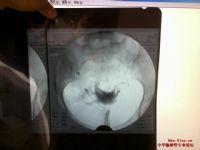

1.B超連續檢測。於圍排卵期第8~9天起。每日用陰道B超連續觀察了解卵泡發育動態情況,若有優勢卵泡形成,達成熟卵泡標準(卵泡最大直徑>18mm晰透亮、邊界清楚等),而無排卵表現,即卵泡持續不消失或無明顯縮小(卵泡滯留型),或繼續增大(30~45mm,卵泡持續長大型),子宮直腸陷凹無游離液出現,即可考慮為未破裂卵泡黃素化(LUF)周期。在B超監測周期中,應由專人專機檢查,以統一標準,避受將排卵後的囊性黃體誤認為LUF。

2.腹腔鏡檢查。對疑有未破裂卵泡黃素化時,行腹腔鏡檢查可進一步確診。一般認為在排卵後1.5天內排卵征依然存在,此後會逐漸封閉,於4~5天完全上皮化,排卵孔封閉。故於黃體早期(月經周期第20天前,BBT上升2~4天)用腹腔鏡直接觀察卵巢面,見有黃體但無排卵裂孔。